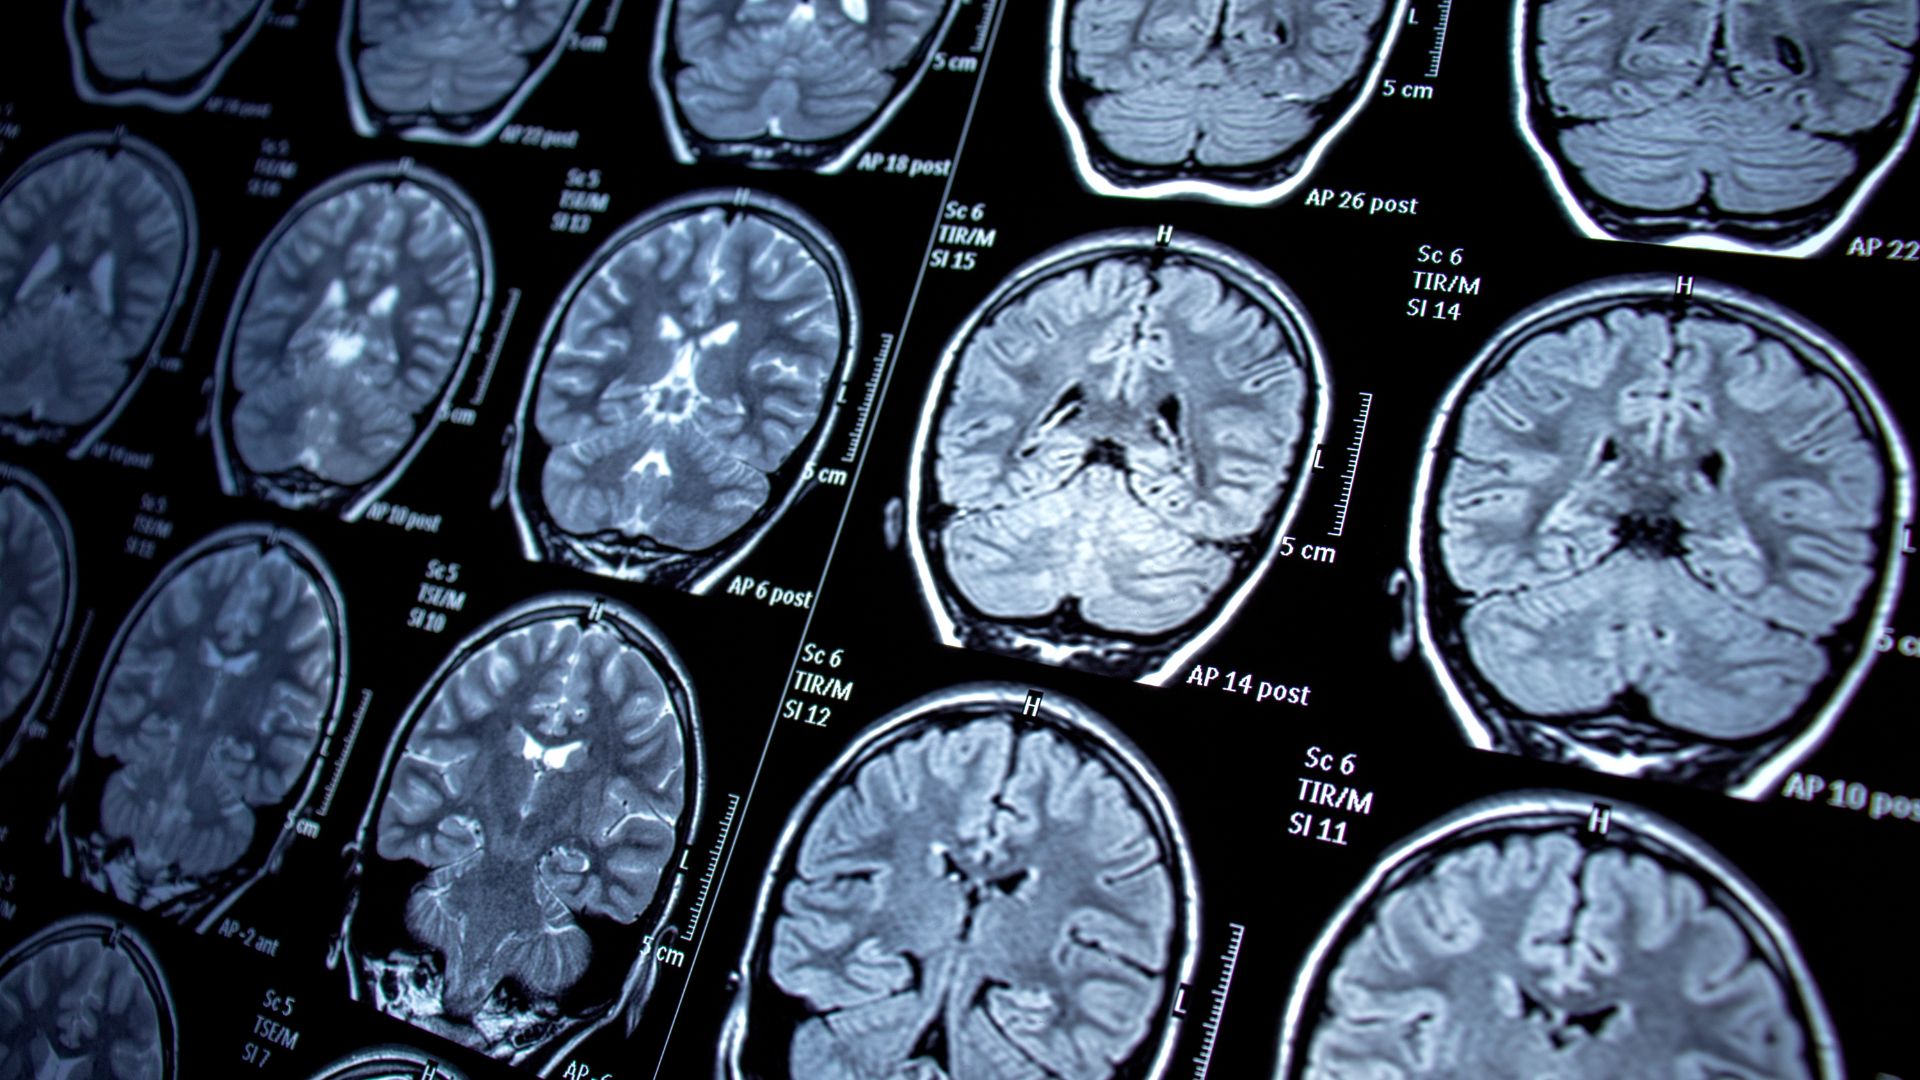

MRI hoạt động dựa trên từ trường mạnh và sóng radio để tạo ra hình ảnh chi tiết của các cấu trúc bên trong cơ thể. Phương pháp này không sử dụng tia X hay chất phóng xạ, do đó được đánh giá là an toàn khi cần chụp lặp lại nhiều lần.

Ưu điểm nổi bật của MRI là khả năng phân biệt mô mềm rất tốt. Nhờ đó, các cấu trúc như não, tủy sống, dây chằng, cơ, sụn khớp hoặc các cơ quan vùng chậu được quan sát rõ ràng hơn so với nhiều kỹ thuật khác. Tuy nhiên, MRI chủ yếu phản ánh hình thái và cấu trúc, ít cung cấp thông tin về hoạt động chuyển hóa của tế bào.

MRI phát huy tối đa giá trị trong các bệnh lý cần đánh giá chi tiết cấu trúc mô mềm. Những tình huống liên quan đến não bộ, tủy sống, hệ thần kinh, cơ xương khớp hoặc các cơ quan vùng chậu thường được chỉ định MRI để quan sát rõ mức độ tổn thương.

Ngoài ra, MRI còn hữu ích trong việc theo dõi tiến triển bệnh lâu dài nhờ ưu điểm không sử dụng bức xạ ion hóa. Điều này đặc biệt quan trọng với những người cần chụp nhiều lần trong quá trình theo dõi hoặc kiểm tra định kỳ.

MRI phù hợp khi cần hình ảnh chi tiết tại một vùng cụ thể, đặc biệt là các cấu trúc mô mềm phức tạp. Những trường hợp cần đánh giá chính xác hình thái, kích thước, ranh giới tổn thương hoặc theo dõi lâu dài thường ưu tiên MRI.

Ngoài ra, với những người cần hạn chế tiếp xúc với bức xạ, MRI là lựa chọn an toàn và hiệu quả. Việc chụp lặp lại nhiều lần cũng ít gây lo ngại hơn so với các phương pháp có sử dụng tia X hoặc chất phóng xạ.